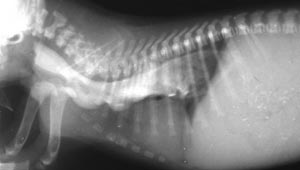

Hereditary esophageal dysfunction is a condition in which there is delayed maturation of the nerve supply to the esophagus so that ingesta (food) accumulates in the esophagus before moving into the stomach. Presumably this is due to insufficient neural innervation of the esophageal muscle so that this muscle fails to push the ingesta into the stomach properly. Affected pups regurgitate soon after swallowing but feeding with the body in a vertical position aids passage of ingesta into the stomach with the aid of gravity. With adequate nursing care such pups can survive and with maturity attain near normal esophageal function.

Contrast radiology using the barium swallow technique has been used to study the condition. The image on this page is from a pup that belonged to a colony of Miniature Schnauzer dogs in which the condition was followed through 5 generations. (Cox, et. al., AJVR 41:326-330, 1980). Many pups in this colony were fed with a stomach tube until weaned.